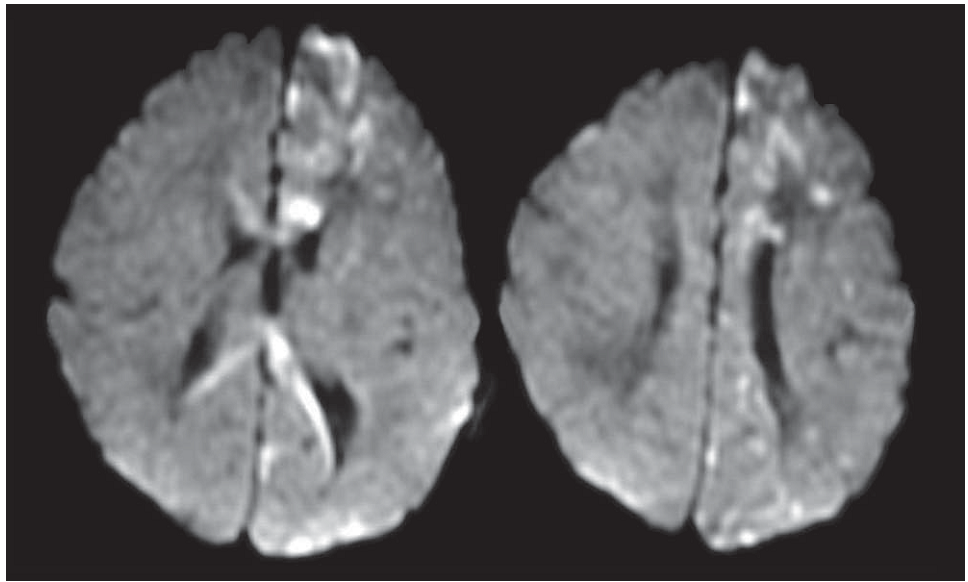

无并发症娩出的一新生儿,女性,被发现身上有皮疹,由半线性成排的水泡和色素沉着过多的丘疹组成(图1)。神经系统查体无殊。对其母亲检查发现左膝后方有轻度色素减退以及包括钉状上门齿在内的异常牙列。患儿4天时出现右侧肢体发作,表现为阵挛性的不同步的面部,上臂和腿部的抽搐。头颅磁共振提示大脑深部和皮质下白质多发弥散受限信号(图2),左侧半球较右侧更甚。临床诊断考虑色素失调症。建议行遗传学检测,但患儿母亲拒绝。

(图2:DWI提示弥散受限)

30%的患者可有神经系统症状,最常见的表现为癫痫发作,生长发育延迟和轻瘫。神经影像学可提示脑萎缩,脑穿通畸形,出血坏死,脑积水和白质病变。越来越多的MRI和MRA证据表明,微血管的缺血性梗死可能是促成神经系统症状出现的潜在重要因素。一些色素失调症患者可有相关的视网膜血管病变,可支持上述可能的血管病理机制。炎症也被认为可能参与其中,因为其(以嗜酸性炎症性水泡皮肤病变的形式)与缺血性卒中在新生儿期同时发生,但罕有神经病理学的证据。其他可能还包括原发破坏性或感染性发病机制。